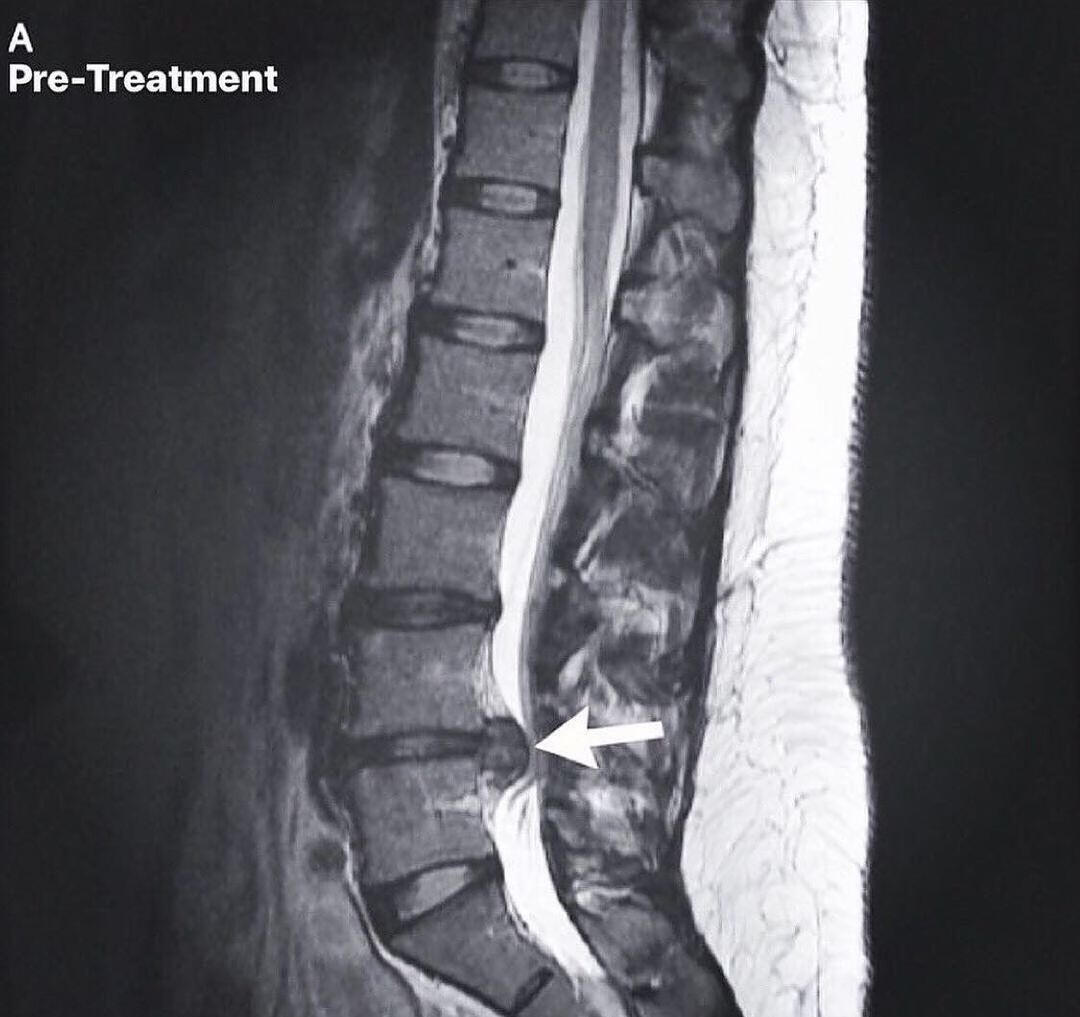

Spinal disc injuries require more than symptom-based care. Our spinal disc rehabilitation approach in Inver Grove Heights focuses on restoring movement, reducing pressure on the disc, and improving how the spine and nervous system work together over time. Care is guided by imaging, clinical findings, and measured progress, not guesswork or force.This care is designed for people dealing with disc herniations, disc bulges, sciatica, chronic back or neck pain, and those who have not improved with traditional chiropractic care. It is also appropriate for individuals looking for non surgical disc care before considering injections or surgery.